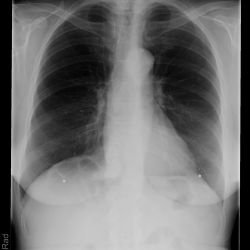

Chilaiditisyndrom